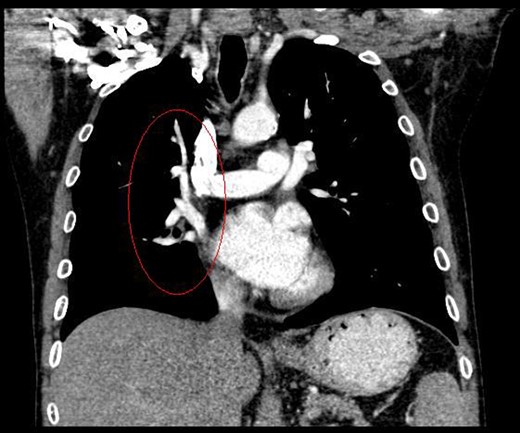

During discussions at the multidisciplinary team meeting, the computed tomography scans of his thorax were reviewed by our radiology colleagues and an anomalous right upper lobe vein was identified.

The patient underwent a right postero-lateral thoracotomy. The right upper lobe pulmonary artery and vein were identified and divided with vascular Endo GIA™ staples. Lymphadenectomy was performed in the draining lymph nodes and we proceeded to isolate the upper lobe bronchus. Prior knowledge of an anomalous venous drainage of the upper lobe made us adopt a cautious approach during dissection posterior to the right upper lobe bronchus and a vascular structure was identified that could be traced in the left atrium; thus, it was found to be an anomalous upper lobe pulmonary vein. The anomalous vein was divided with vascular Endo GIA™ staples. The bronchus was divided with a TA™ stapler.

The patient recovered well postoperatively and was discharged home. Histologically, the patient's tumour stage was pT1aN0 (Figs 1–6).

Kim et al. [2] first reported the contrast-enhanced computed tomography findings of aberrant pulmonary veins, which were observed as a focal nodularity attached to the posterior wall of the bronchus intermedius. Pulmonary vein variations are usually seen in the common pulmonary vein and the middle lobe vein draining into the inferior pulmonary vein or the left atrium [3]. There are only a few CT studies of the upper lobe vein. The frequency is reported between 1.7 and 5.7% [3].

Kim et al. [2] eluded that in 5% of normal subjects, the right superior segmental pulmonary veins had an aberrant course also either to the inferior pulmonary vein or directly to the left atrium. Asai et al. [4] noted that in right lung resection surgeries, there was a 5.7% occurrence of abnormal right upper lobe venous drainage.